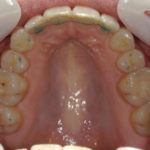

Arcade maxillaire avant traitement orthodontique, séquelles de maladie parodontale

Après traitement orthodontique et réalisation d’une attelle coulée collée (courtoisie Dr Patrick Fournier)